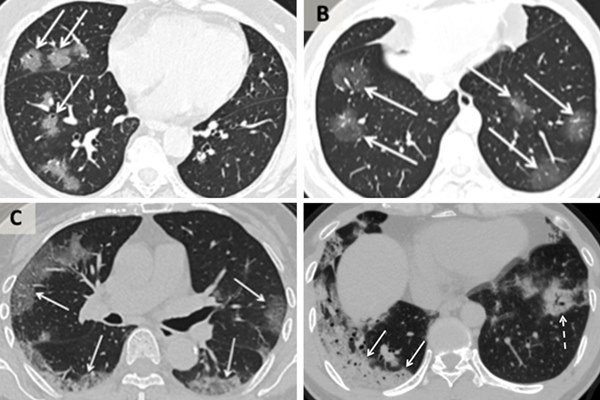

Nghiên cứu này và nghiên cứu của bác sĩ Xiao cho thấy khi bệnh tiến triển, ảnh CT cho thấy "các vệt thủy tinh mờ", một loại màng che ở các bộ phận của phổi có thể thấy rõ trong nhiều loại bệnh nhiễm trùng đường hô hấp do virus.

Những khu vực mờ đục đó có thể phân tán và dày lên khi bệnh nặng hơn, tạo ra thứ mà các bác sĩ chụp X-quang gọi là màng bao dày đặc trên máy quét.

Ảnh chụp CT của các bệnh nhân Trung Quốc bị nhiễm virus corona. Theo chiều kim đồng hồ từ trên cùng bên trái, một phụ nữ 56 tuổi, một nam 44 tuổi, một nam 42 tuổi và một nữ 65 tuổi.